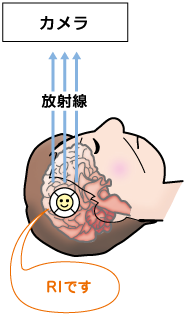

脳の検査 脳血流シンチグラフィを受けるにあたって 日本メジフィジックス株式会社